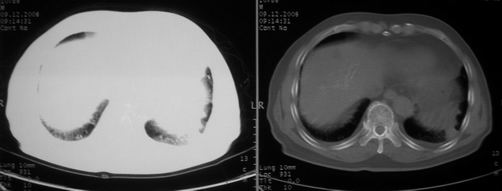

男,78岁,咳嗽、咳痰、发热入院,抗炎治疗一周后已退热,咳血似痰。

10月9日片:

ct左肺下叶大片状高密度影,病变密度不均,界限不清,左侧胸腔积液,治疗后复查临床症状好转而影像学表现病变有发展,还是首先考虑感染性病变,复查时间短附合感染性病变的病理改变。

两肺炎症感染(以左肺下叶为著),双侧少量胸腔积液;建议继续抗炎治疗。